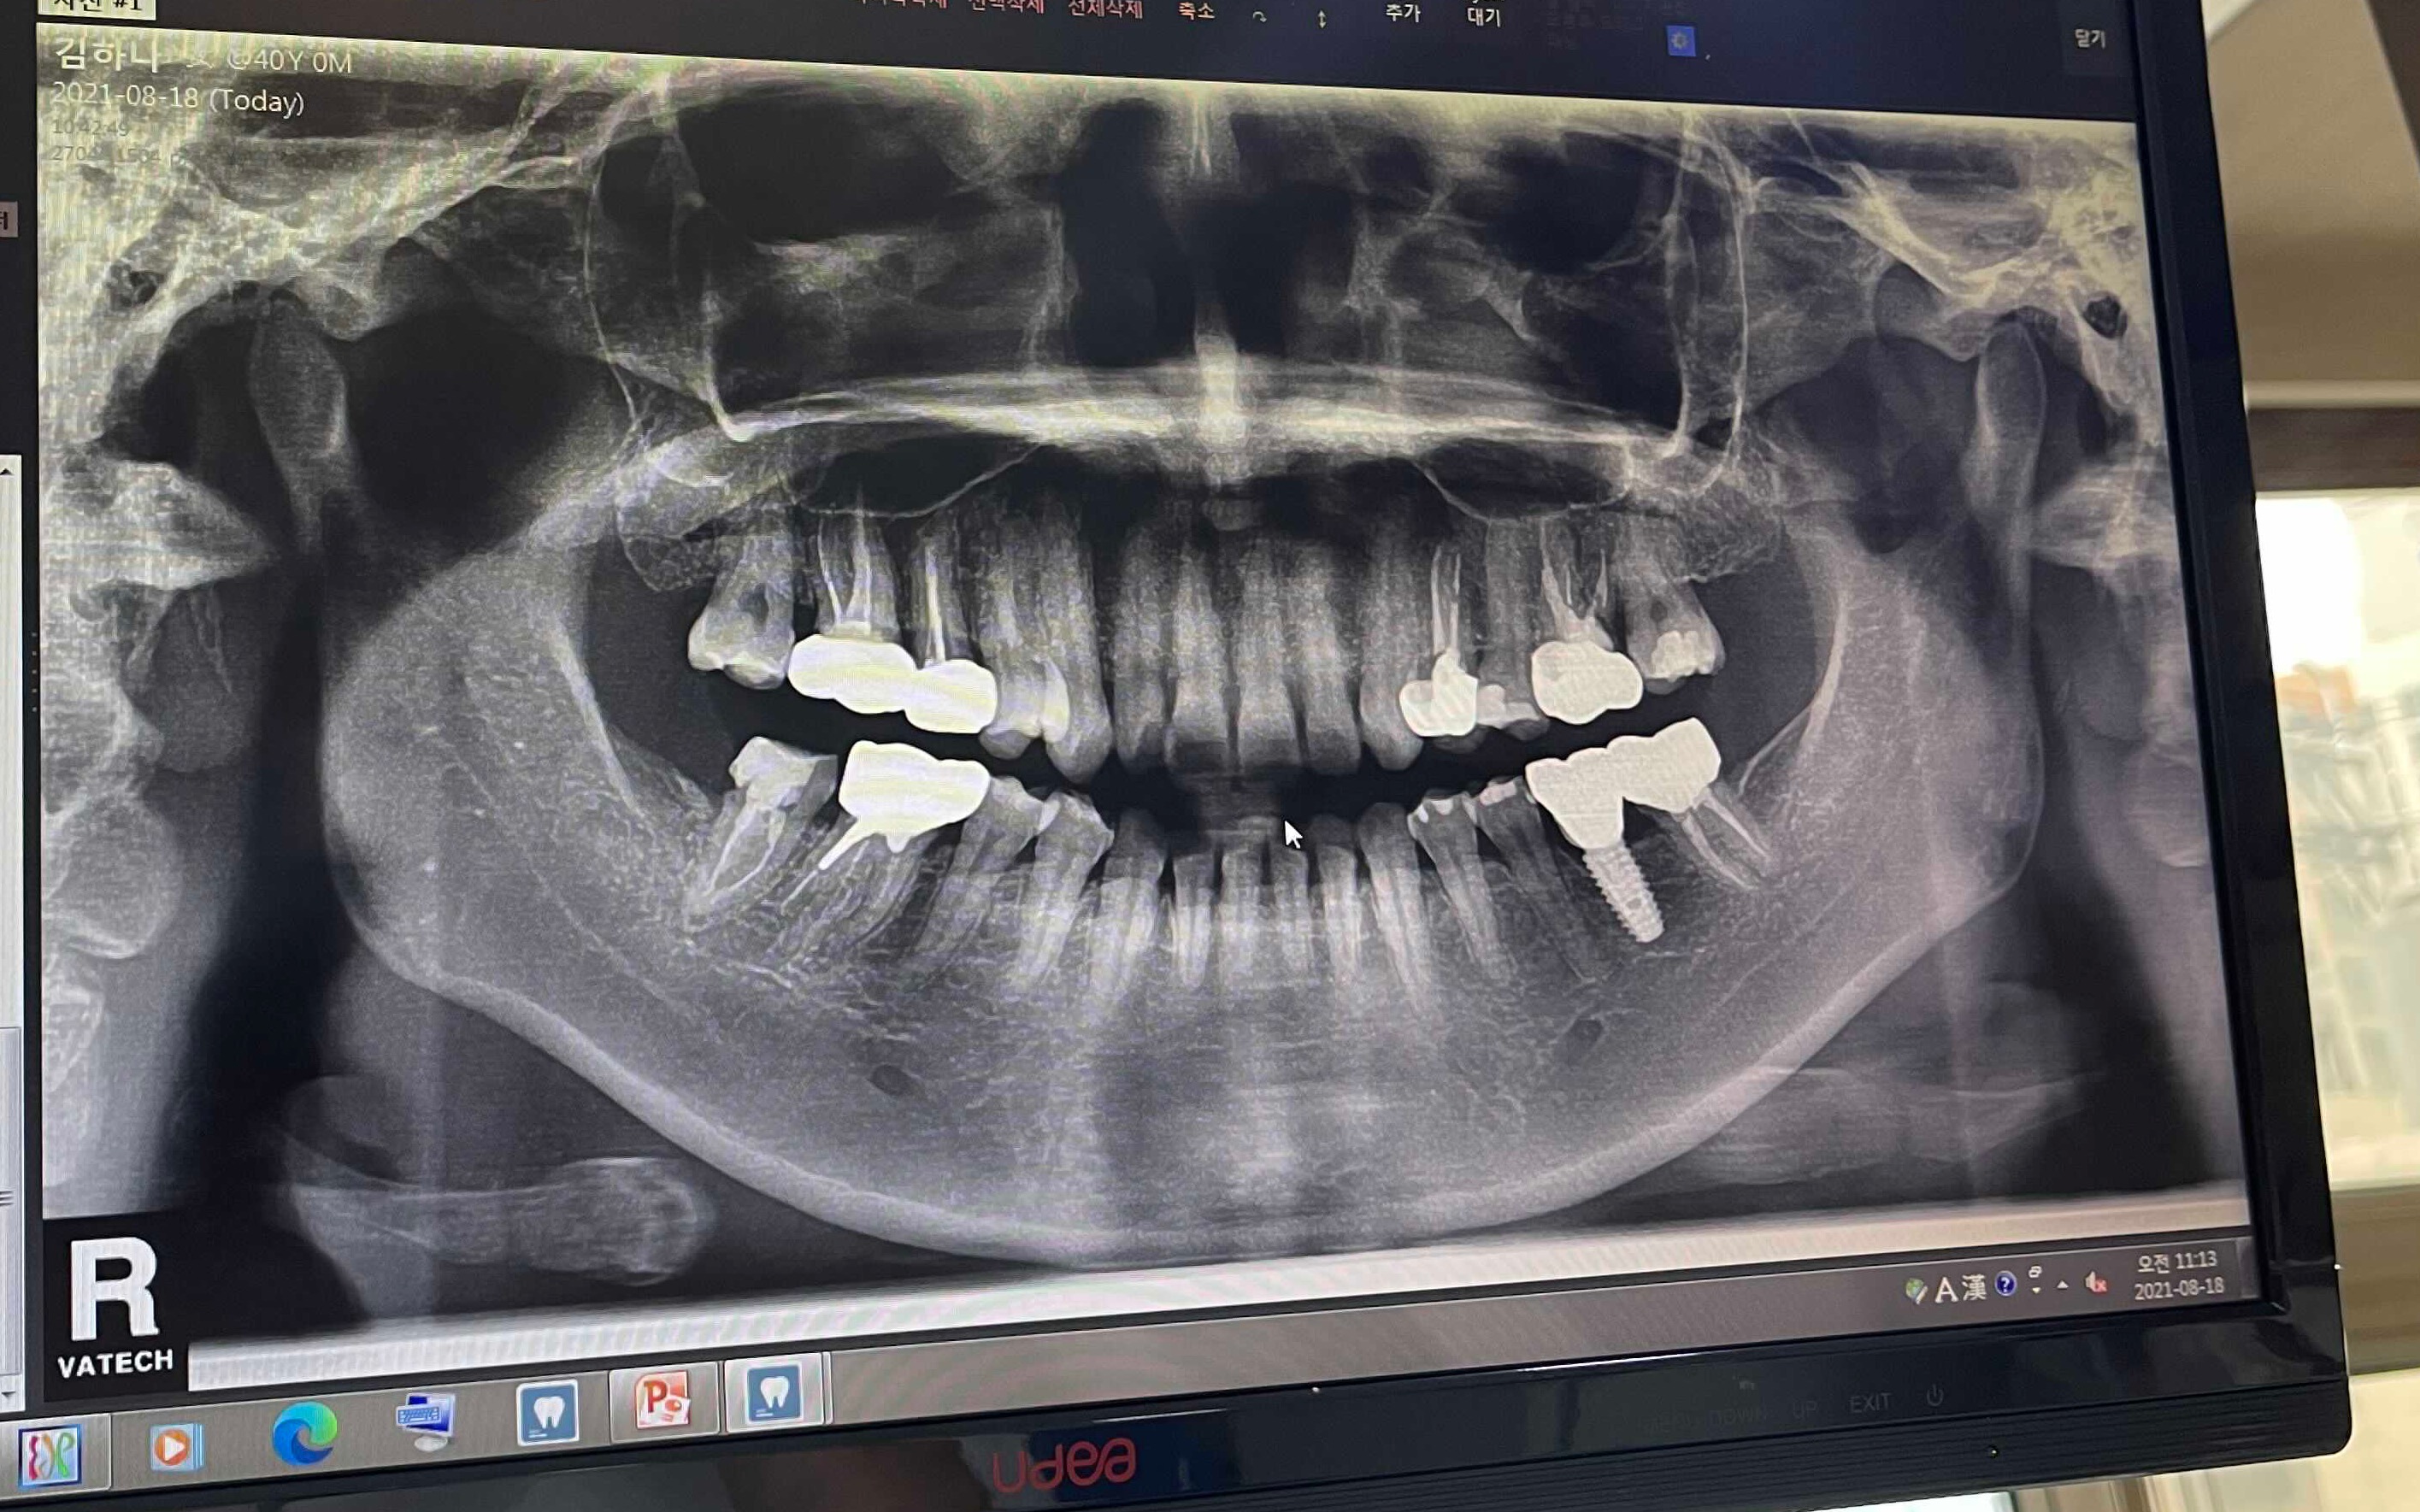

견적이 300넘게 나온 이유는 아래 사진을 보시면 아시겠죠

어마어마 하게 했습니다.

나이 마흔도 되기 전에

그때가 서른여섯이었던가 ㅜㅜ

스켈링…이 아니라

임플란트를 했습니다.

이편한치과에서 임플란트한 치아,

불편하지 않냐 물으신다면

일부러 생각해서 찾으려고 안하면,

어떤게 임플란트한건지 저는 모르고 삽니다.